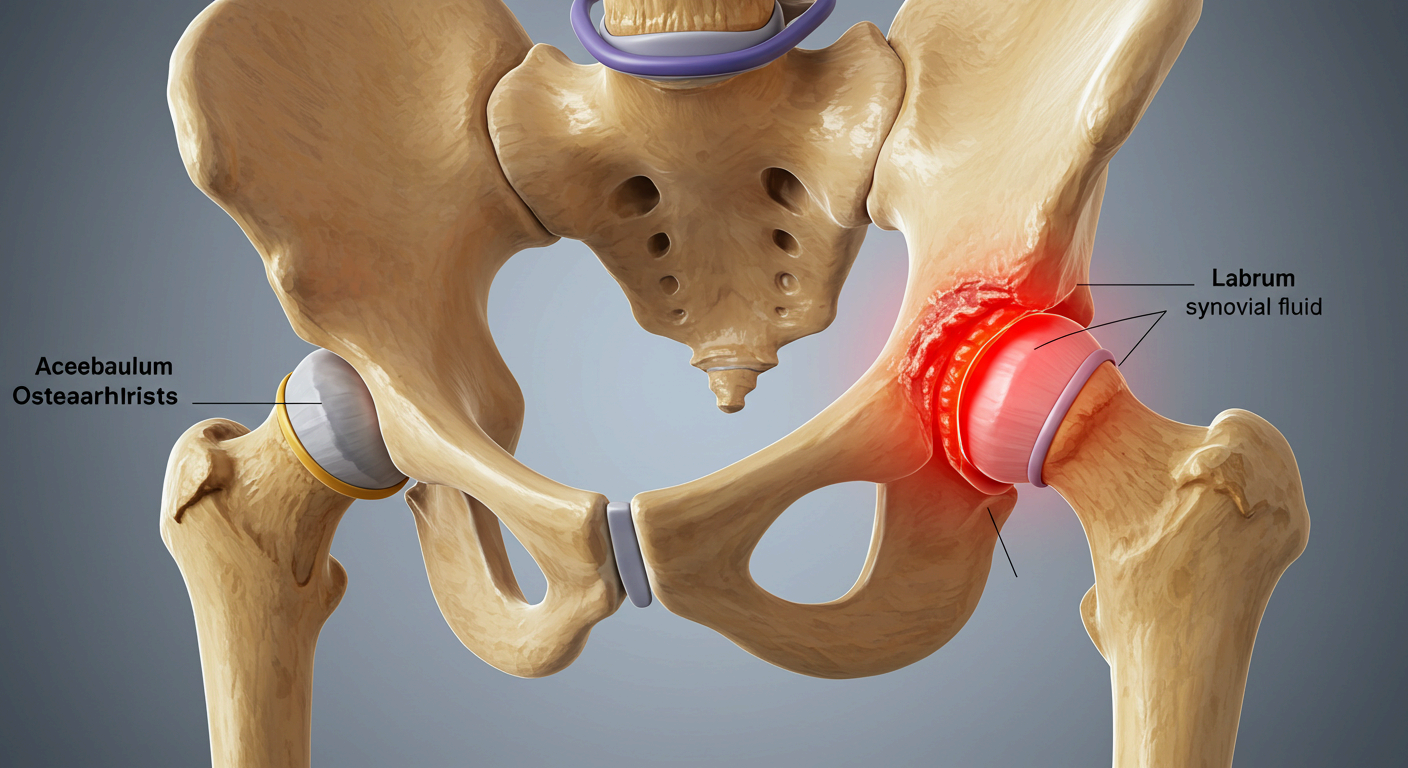

📌 고관절 충돌 증후군 (FAI)

- 대퇴골두와 비구가 부딪히는 구조적 이상으로 통증 유발

- 주로 젊은 운동선수나 활동량이 많은 사람에게 발생

📌 퇴행성 고관절염

- 고관절 연골이 닳아 없어지며 뼈와 뼈가 직접 마찰됨

- 50대 이상에서 흔하며, 통증·운동 제한·관절 소리 등이 특징

📌 고관절 이형성증

- 선천적으로 고관절의 형성이 불완전하여 관절 불안정과 통증 유발

- 유아기에 진단되는 경우도 많고, 성인기에 퇴행성 질환으로 이어질 수 있음